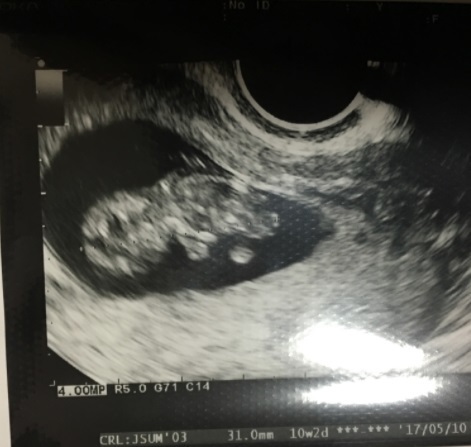

10週3日(10w3d・性別不明)|なぁひろ さん(20歳)

エコー写真撮影時のエピソード:

前回卵みたいな形だったのが初めて頭や足が見えて、ちゃんと成長したのが目に見えて分かって、愛おしく思えた。鉄分を取るようにしたり、葉酸のタブレットを買ったり、好きだったお寿司や生物を食べないように気をつけるようになった。パパもエコー写真を見て父親の自覚が出てきた。